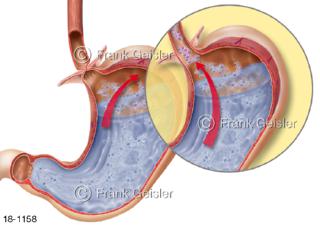

18-1158 Sodbrennen Reflux Refluxkrankheit Magen Speiseröhre, Rückfluss saurer Mageninhalt